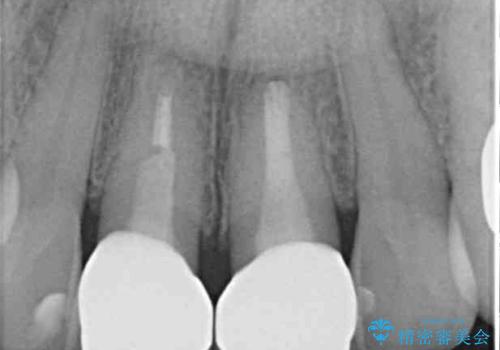

根管治療後に痛みは軽減しましたが、僅かな痛みが続くとのことで、レントゲン写真では病変は認められなかったものの、歯根端切除を行うこととしました。処置後は痛みは全くなくなり、安心して補綴治療を行うことができました。